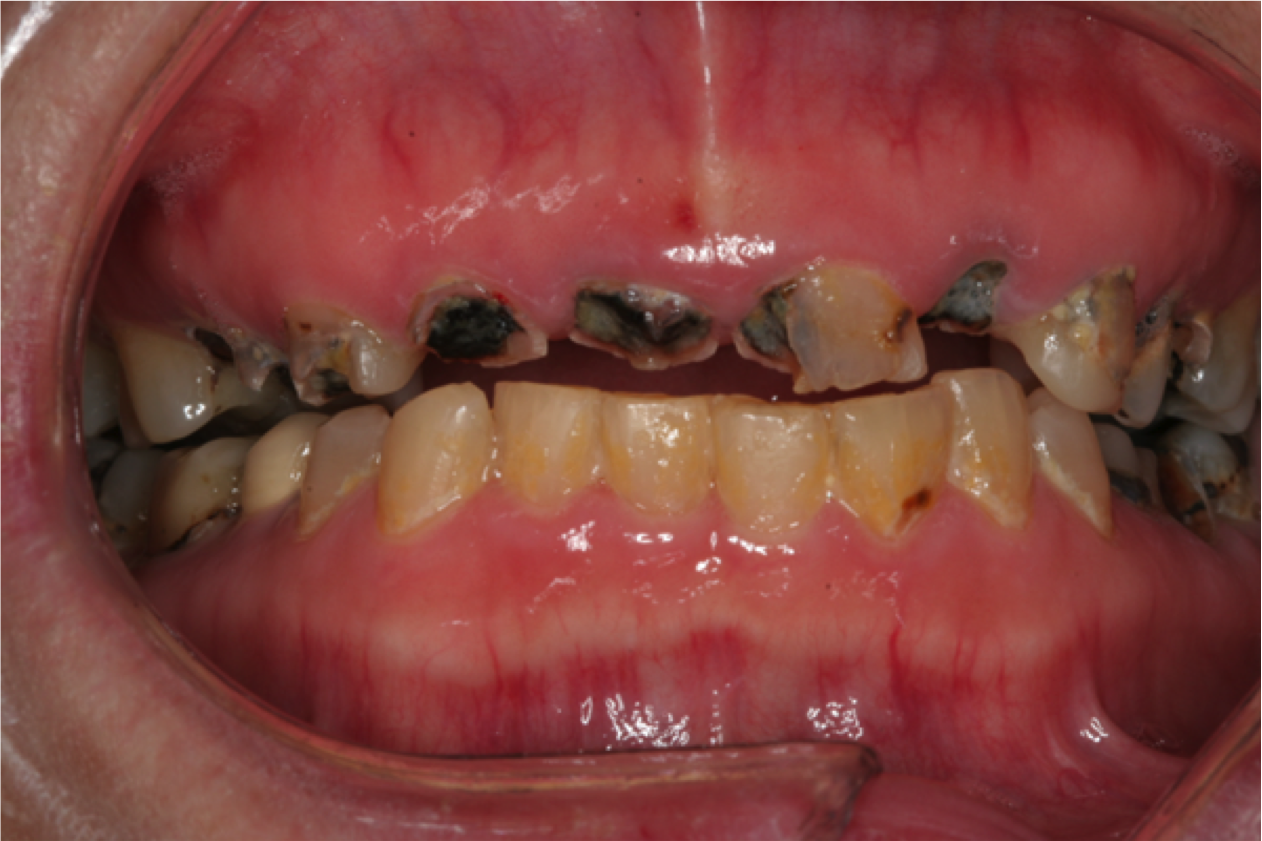

Rapidly advancing and rampant caries can result in pain, acute and chronic infections, and tooth loss leading to resultant functional, esthetic, and psychological sequelae of poor oral health.25 Left untreated, root caries can result in the loss of the crown and a retained root that can be a chronic source of inflammation (Figure 2). This, in turn, causes exposure of the pulp chamber, creating a risk for chronic and acute apical periodontitis.20

Fig 2. Rampant caries and nonrestorable root tips.